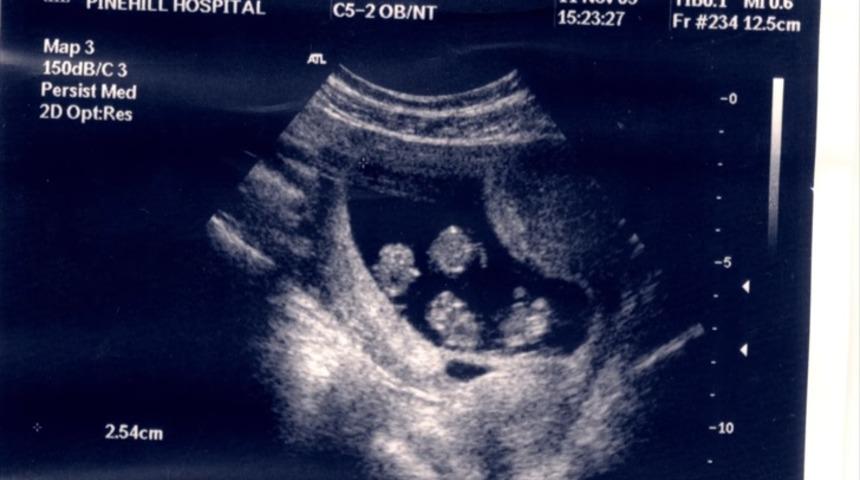

Julie tedavi sonrası hamile olduğunu öğrendi. İkizleri olacağını düşünen çift ilk ultrason incelemesinde dördüzleri olacağını öğrenince neye uğradıklarını şaşırdılar.

Julie, tek yumurtada 4 aynı embriyoyu taşıdı, embriyolar aynı plasentayı paylaştı. Julie bu durumu yaşayan dünyadaki 27 kadından sadece biriydi.